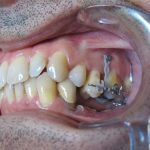

Arcade mandibulaire avant traitement orthodontique, séquelles de maladie parodontale